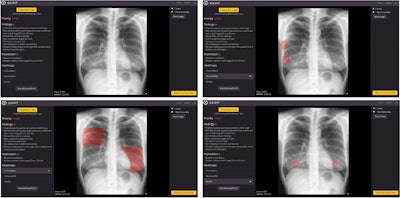

Image of patient (upper-left) in which, according to the radiologist's report, there is only consolidation, but the algorithm detects an abnormal rib (upper-right), consolidation (lower-left), and two nodules (lower-right). It is worth noting the confusion of a consolidation with mammary tissue and of two nodules with the two mammary areolae. Image courtesy of Scientific Reports.